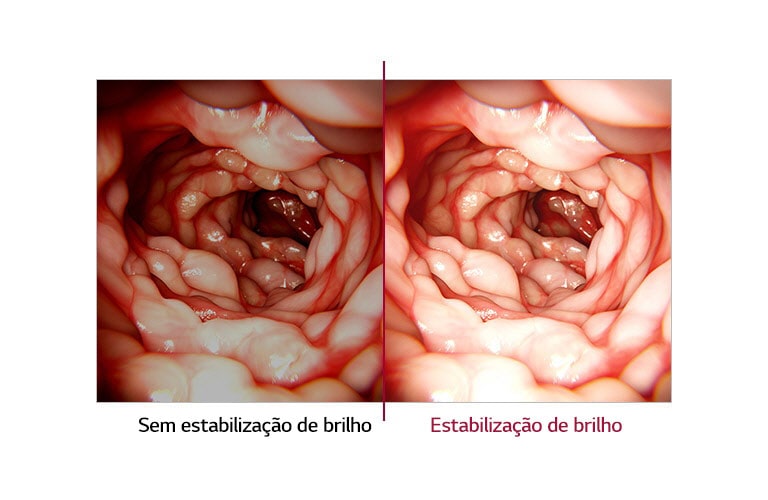

Estabilización del brillo

SIM